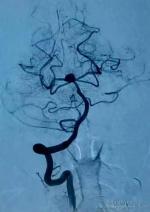

赵洪洋《德国神经外科临床见闻——我的全新体验》(杨建松播讲)